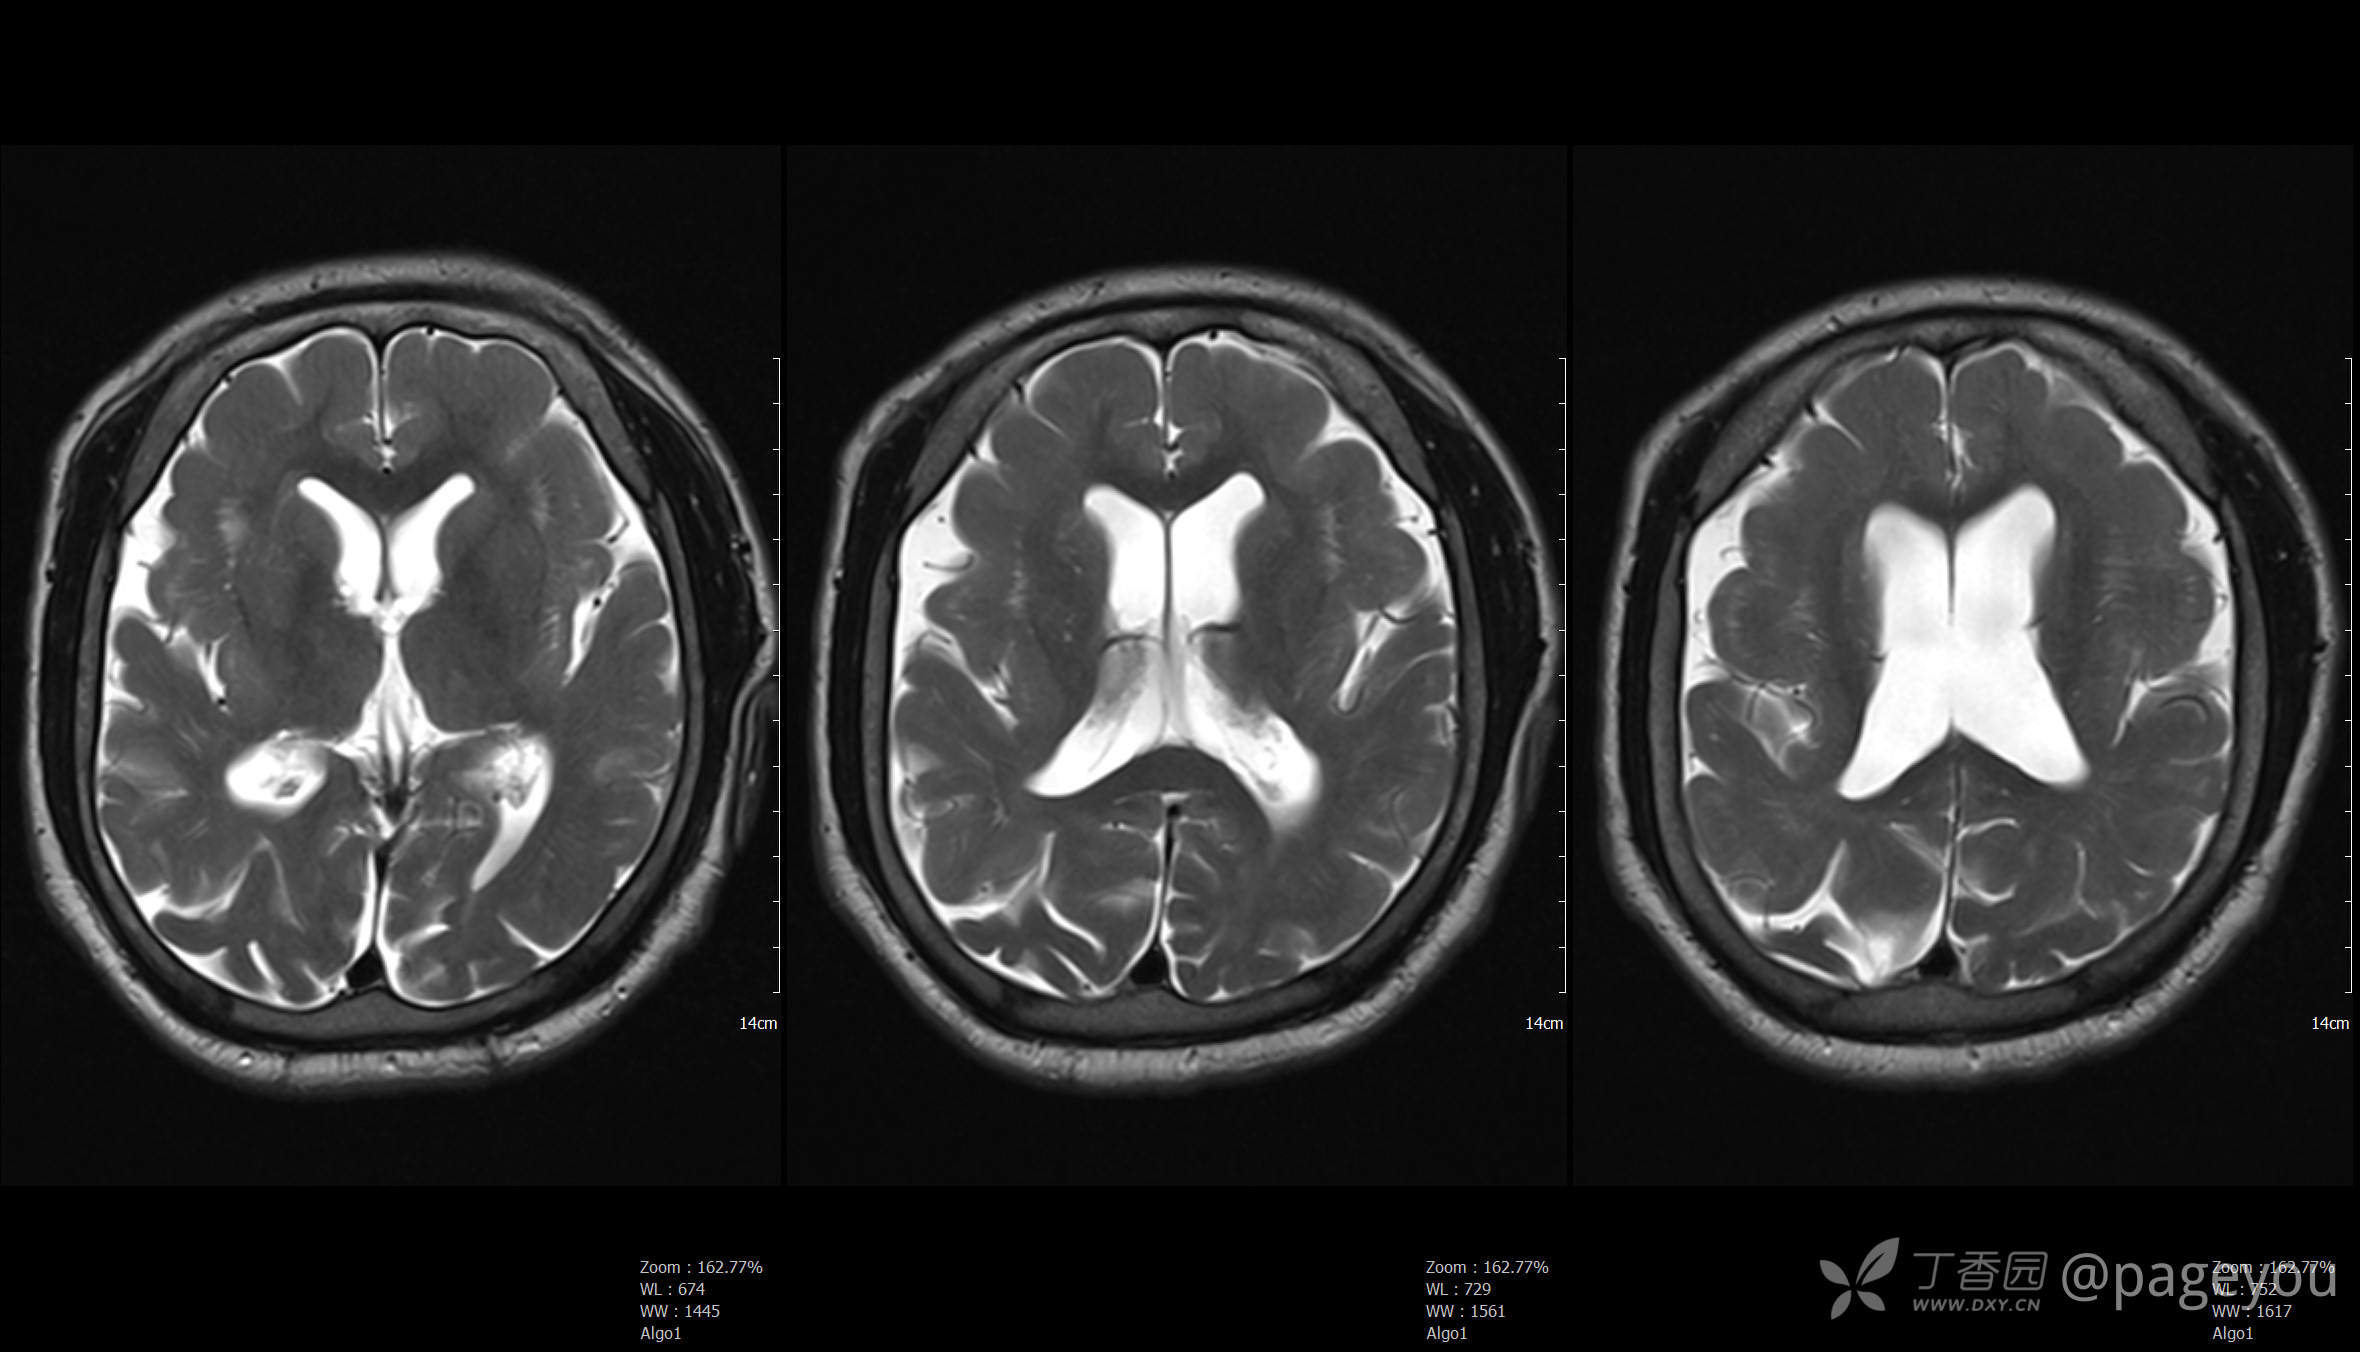

头颅MRI: